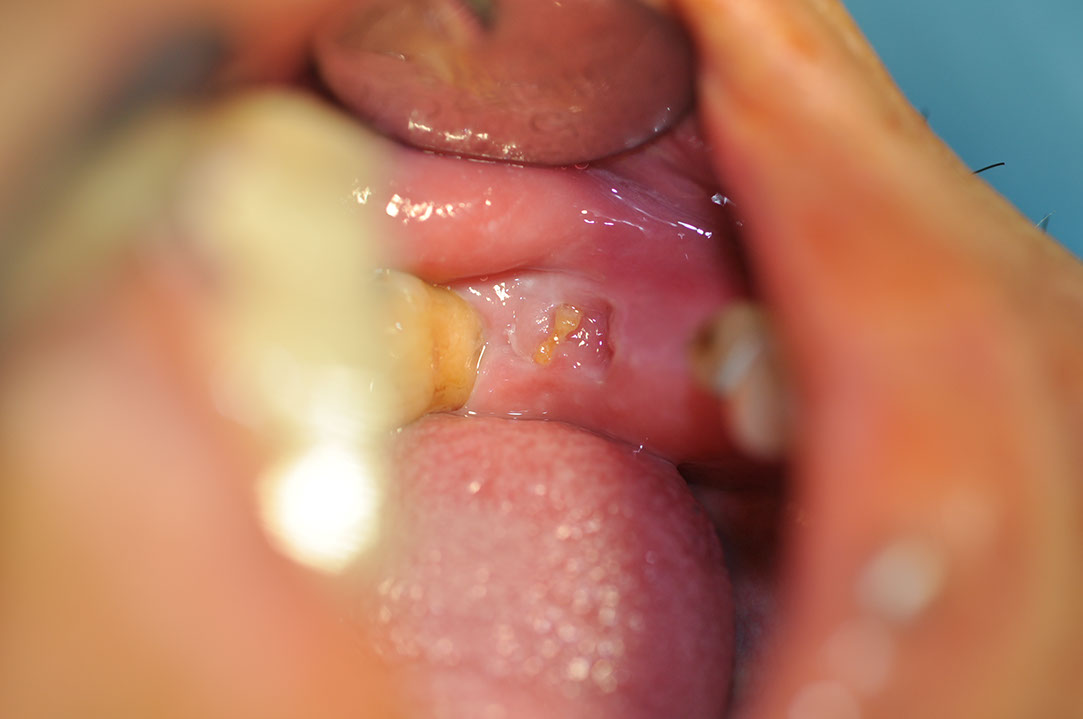

Implant 116a3.JPG